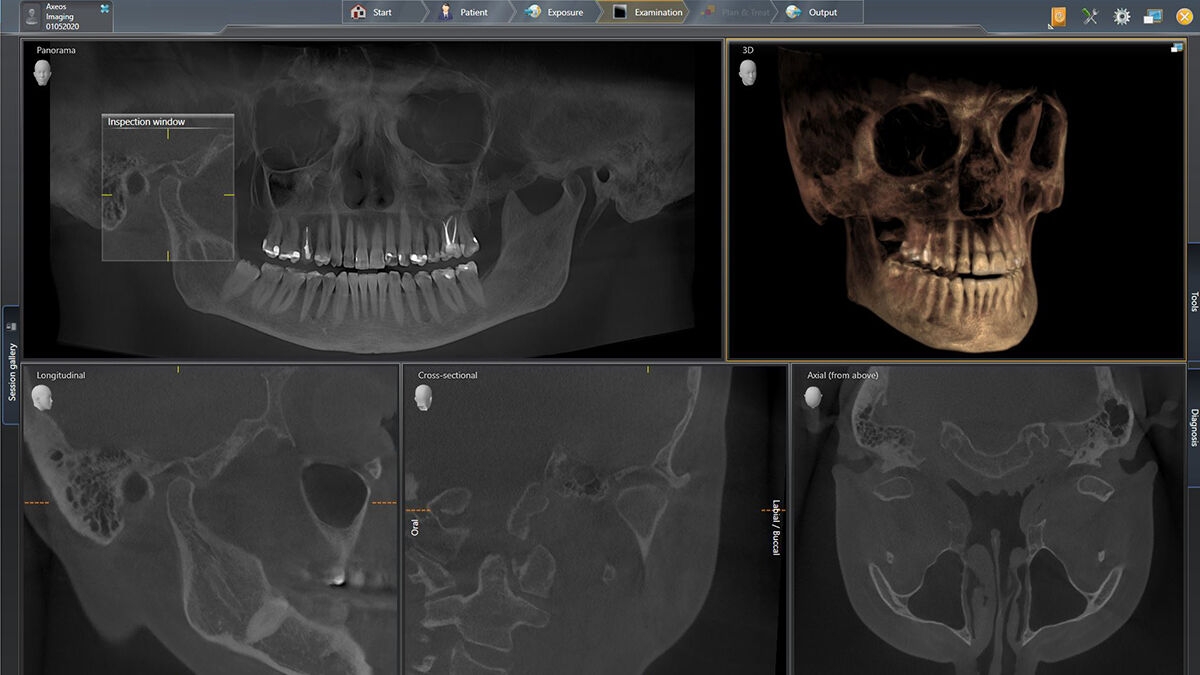

A reliable diagnosis is the most important thing at the beginning of any treatment. It should be precise, yet quick. To facilitate this, we use state-of-the-art technology to expand your spectrum - from the overall picture down to the smallest detail, for outstanding image quality at the lowest dose achievable and optimized visualization. This gives you more reliability in your image analysis and the final diagnosis, in both 2D and 3D.

The versatile 2D/3D hybrid unit with a big FOV and high image quality for practices with a wide treatment spectrum. Axeos convinces not only with its high-caliber performance, but also with its focus on comfort and design as well.

The high-end 2D/3D hybrid unit features revolutionary technology and patented positioning solutions. An optional ceph arm provides additional benefits, adding to the already broad range of offerings.

This All-round 2D/3D hybrid unit offers a full range of capabilities to support all of the 2D and 3D tasks in your practice. Thanks to its flexible volume sizes and adjustable dose options, you have a great partner to support your workflows.